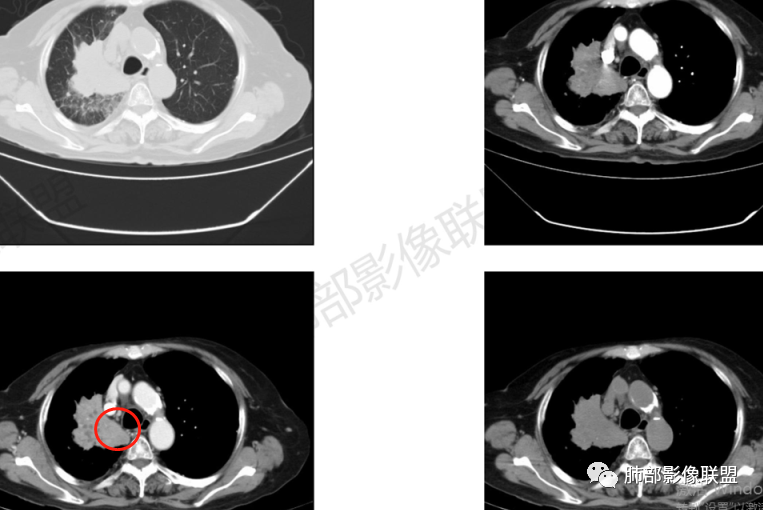

临床信息:老年女性,亚急性病程,咳嗽发热。有激素使用史。既往有淋巴结结核病史。肿瘤标记物Ca125升高。血沉升高,C反应蛋白轻度异常。 影像所见:右侧胸廓相对狭小,右肺上叶不规则团块影贴附纵隔旁,轻度分叶,整体密度较均匀,偶见钙点。

相应上叶尖端及前段支气管开口未能追踪(阻塞),开口处见钙化。病灶渐进性强化,并衬托出较完整尖段及前段含液支气管影。支气管开口区域未见异常高密度强化(如类癌等)及相对乏血供区(如鳞癌)。病灶区未见液化坏死。右上纵隔及胸廓入口区未见病灶胸膜外突破(栽赃)。

右肺上叶后段等区域散在片状影,边界不清(提示渗出性病灶)。

纵隔及双肺门见钙化淋巴结。心包积液,右侧胸腔积液(提示存在活动新病灶)。双侧胸膜下见多发斑点状钙化,胸廓变形(提示存在结核基础病变可能)。 诊断意见:综上,右肺上叶块状影更符合继发性肺结核。 最后小结:既往诊断淋巴结结核,提示已治愈。近2年服用激素,可疑诱导结核复燃,也可引起发热。纵隔肺门淋巴结肿大钙化,压迫支气管,右肺上中下叶支气管均狭窄,所以引起喘息咳嗽。尖段支气管受累闭塞,导致肺不张、支气管粘液栓,出现条状无强化区。病变累及胸膜,导致结核性胸膜炎并胸水,引起右侧胸痛。实验室检查血沉快,CA125高,低蛋白,均符合结核。下一步,建议支气管镜尖段支气管刷检并抗酸染色。(本段摘自於雄老师精彩发言)